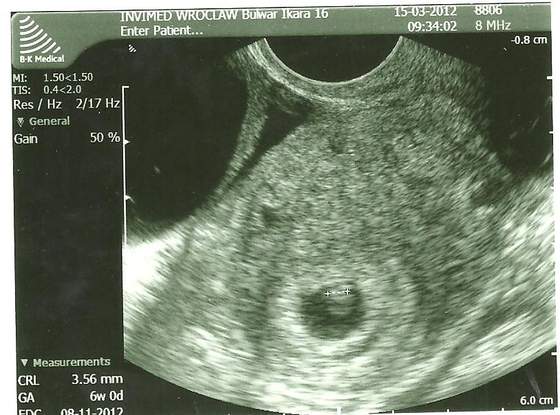

Pierwsza wizyta w 6t2dc - serduszko bije, maleństwo ma 3,5 mm

a oto i moja kropeczka

Dopisuje moje dzisiejsze USG 3D wykazało bicie serduszka!!!! bije mocno i jak na dzień dzisiejszy jest wszystko ok .